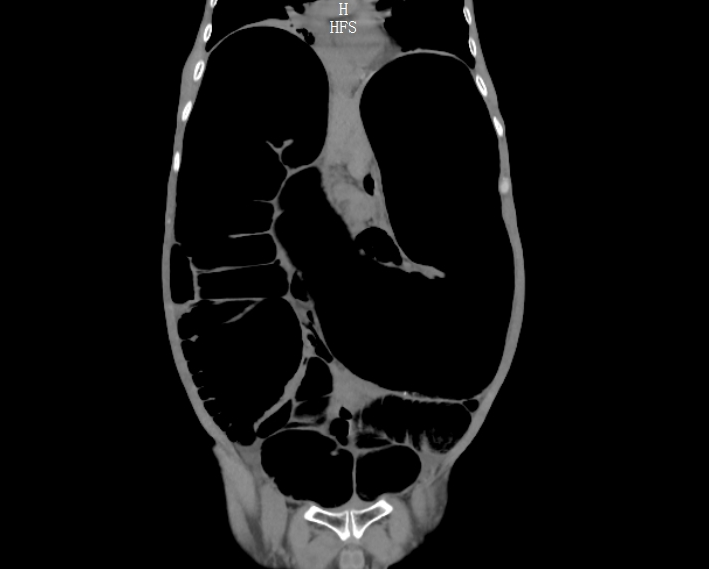

考虑到甘先生身体虚弱,无法配合完成钡灌肠大肠造影,胃肠外科·小儿外科团队给他安排了腹部 CT、DR 和肠镜检查。

结果一出来,答案清晰了:他的升结肠、横结肠显著扩张,像被吹大的气球,胀得异常粗大;可远端的结肠和直肠,却明显狭窄。

结合临床表征,团队初步断定:这不是普通便秘,而是一种罕见病——成人全结肠型巨结肠。